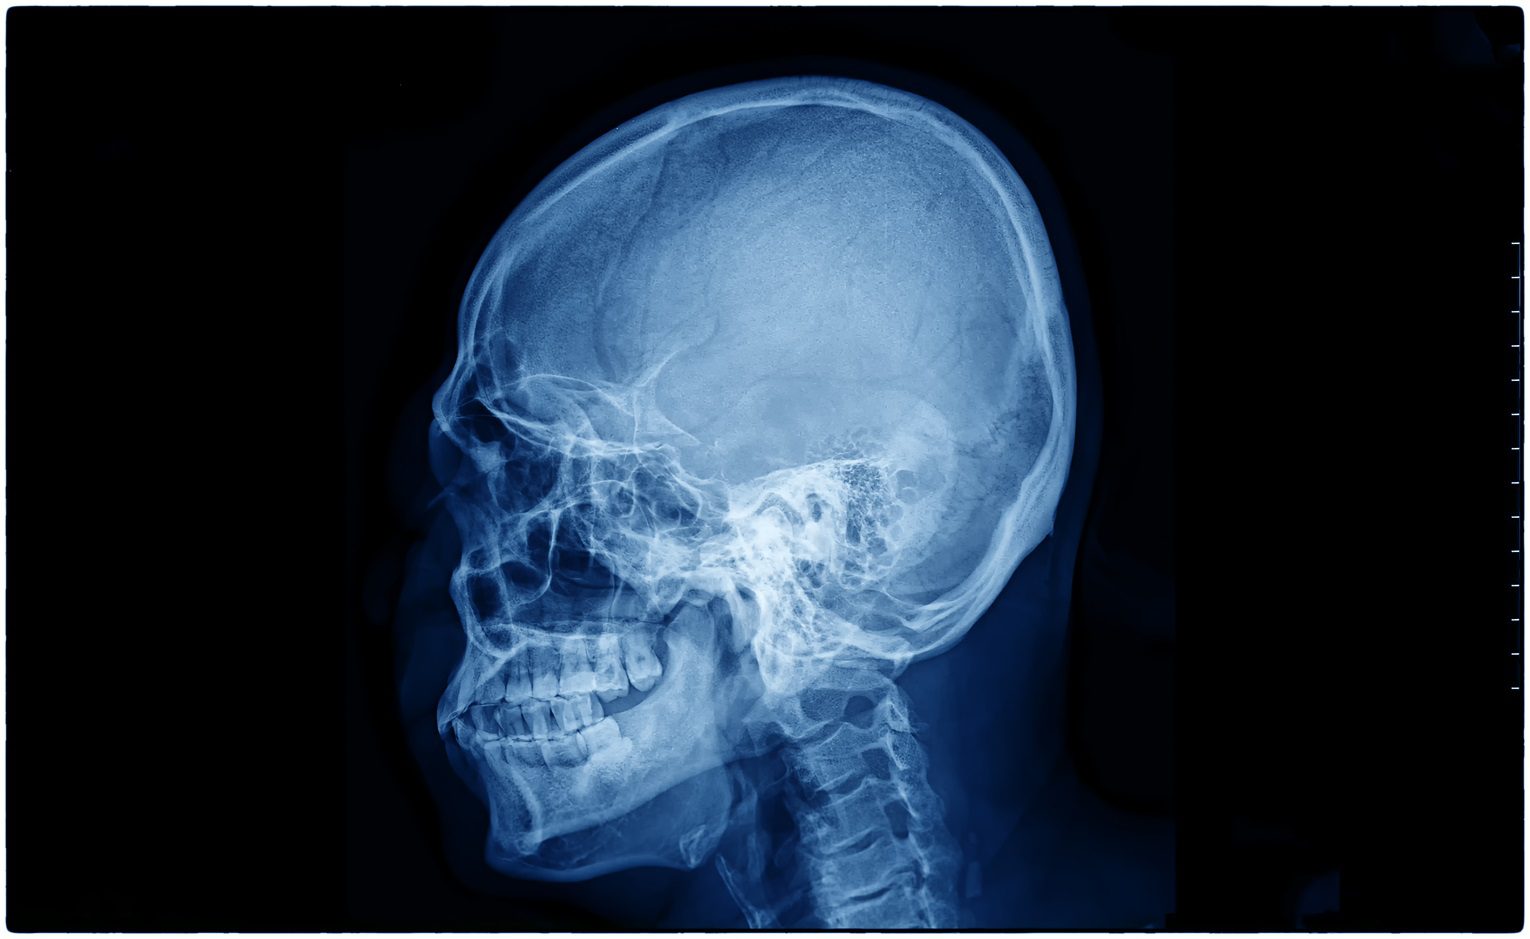

A hemicraniectomia descompressiva é um procedimento cirúrgico utilizado em situações críticas para reduzir a pressão intracraniana causada por um acidente vascular cerebral (AVC) ou outros eventos neurológicos graves. Essa técnica, embora drástica, pode fazer a diferença entre a vida e a morte em pacientes que enfrentam complicações severas, como edema cerebral maciço.

Procedimento cirúrgico

A hemicraniectomia descompressiva é um procedimento complexo realizado por neurocirurgiões experientes. As principais etapas incluem:

- Incisão cirúrgica:

- É realizada uma incisão no couro cabeludo para acessar o crânio.

- Remoção do osso craniano:

- Uma seção do crânio é cuidadosamente removida para permitir a expansão do cérebro.

- Alívio da pressão intracraniana:

- Se necessário, o líquido acumulado é drenado e o cérebro é protegido com uma membrana especial.

- Preservação do osso craniano:

- O segmento ósseo removido é preservado para uma futura cranioplastia, na qual será recolocado após a redução do edema.